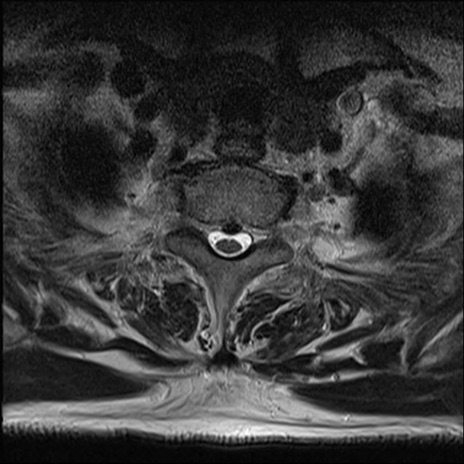

【整形】TIPS症例7 頚椎MRI T2WI(横断像)

頚椎MRI

矢状断像と横断像